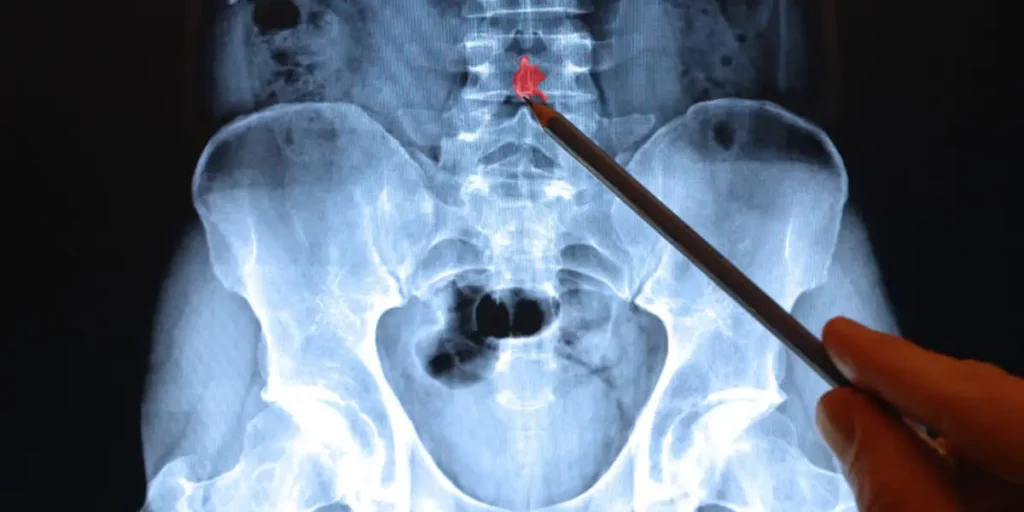

Another way to think of this difference is that the vertebrae of the spine have a much smaller ratio of cortical bone to trabecular bone.

As such, there is proportionally less strong, cortical bone to resist fracture.

In contrast, long bones have a larger cortical bone to trabecular bone ratio meaning that they have more of the dense, tensile strength of cortical bone that helps resist fracture.

In contrast to long bones in the extremities, vertebral fractures tend to occur by an applied compression force down the long axis of the spine or from torsion.

Rather than snapping a stick, vertebral fractures are more like crushing a can or a brick with a hammer.

In addition, the vertebrae as irregular bones tend to be more compact and have many more connections to their neighbors per square inch than long bones.